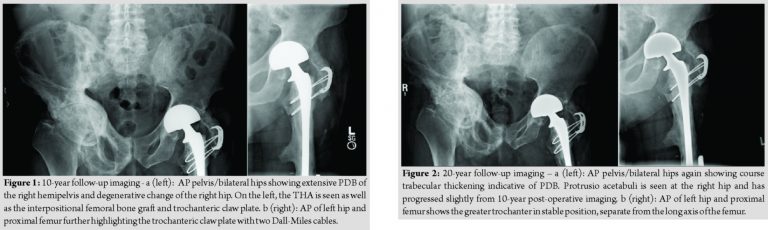

To minimize dislocation risk, a bipolar head was then attached to the femoral trunnion. The composite femoral reconstruction was then reduced and fit nicely into the acetabular component. The native greater trochanter was attached to the proximal allograft with a trochanteric claw device and two Dall-Miles cables, one of which was passed through the allograft lesser trochanter and one below it. The capsule was then repaired, and wound closure was performed in standard fashion. The patient was extubated and transferred to the inpatient floor where he followed an uneventful post-operative course. He was discharged to home after 2 weeks of inpatient rehabilitation with 60 pounds weight-bearing for 3 months. He then progressed to weight-bearing as tolerated with crutches and subsequently with a cane. He returned to full pre-operative activity levels within the 1st year. The allograft native femur junction healed robustly with a significant callus formation. The greater trochanter osteotomy, however, resulted in painless non-union. In the decade following his reconstruction, the patient’s PD progressed throughout his pelvis and left hip and began to invade the medial aspect of the allograft. He was followed by his endocrinologist who treated him with bisphosphonate therapy. He noted minimal left hip or thigh pain after the first 3 months following his reconstruction. He lived at home with his wife, walked with a cane, and cared for his home and yard (Fig. 1a and b). In the 2nd decade following his reconstruction, the invading PD on the medial aspect of the allograft remained stable. There were no signs of loosening of the cement mantle of the long-stem bipolar prosthesis, though the prosthesis itself had migrated somewhat medially. The cables remained intact but had started to cut medially into the allograft. His right hip progressed to moderate arthritis, though he did not complain of pain. He did not have any left hip pain or stiffness (Fig. 2a and b). Twenty years after his reconstruction, the patient was 90 years old and experienced only mild left hip pain worsened with activity. The patient remained relatively active and was able to ambulate independently. The greater trochanter osteotomy remained in stable, asymptomatic non-union. At the post-operative year 21 mark, the left acetabulum began demonstrating radiographic signs of wear with thinning superiorly. At the 24-year mark, the bipolar component began to exhibit signs of early acetabular protrusio. At the 28-year mark, the bipolar component developed further acetabular protrusio. During the entire period of follow-up, the cement mantle within the allograft around the femoral stem remained intact without signs of loosening or subsidence (Fig. 3a, b, c, d). At 28 years post-operative, the patient sustained a right hemispheric stroke that resulted in the left lower extremity weakness. He then transitioned to an assisted living facility. He is presently 99 years old and is mobile with a wheel chair without any left hip or thigh discomfort.